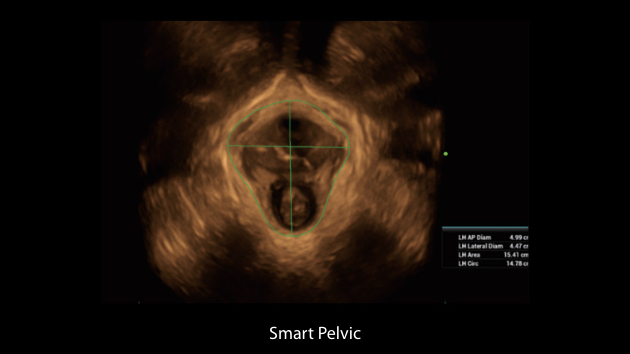

Le Nuewa?I9, con?u spÃĐcialement pour la santÃĐ de la femme et les soins nÃĐonataux, offre une expÃĐrience entiÃĻrement nouvelle gr?ce aux innovations dont il est dotÃĐ, tant à lâintÃĐrieur quâà lâextÃĐrieur. Ces innovations sont dÃĐveloppÃĐes sur la base d'une comprÃĐhension approfondie de scÃĐnarios cliniques complexes, fournissant des rÃĐponses prÃĐcises et adaptÃĐes ainsi qu'une efficacitÃĐ exceptionnelle et une expÃĐrience utilisateur remarquable.

La plate-forme ZST+?est une innovation extraordinaire, reprÃĐsentant une ÃĐvolution de lâimagerie ultrasonore. Elle transforme la formation conventionnelle de faisceaux en un traitement basÃĐ sur les canaux de donnÃĐes. Elle repousse les limites de lâimagerie conventionnelle et du compromis entre rÃĐsolution spatiale, rÃĐsolution temporelle et uniformitÃĐ tissulaire en offrant une qualitÃĐ dâimage exceptionnelle pour des solutions dâimagerie infinies et en constante ÃĐvolution.